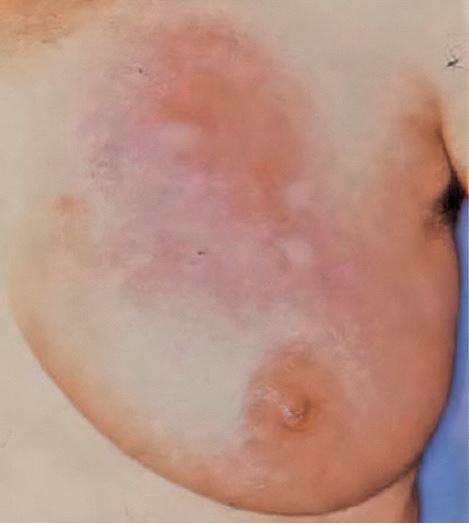

Tab. 2: Tabellarische Zusammenfassung der fünf Kardinalsymptome einer Entzündung. Abb. 1: Idiopathische granulomatöse

Mastitis. Klinischer Befund der linken

Brust mit multizentrischer, quadrantenübergreifender,

teils konfluierender

Hautrötung, kombiniert mit multiplen

kutanen Indurationen über intramammärer

Knotenbildung.Klinisch präsentiert sich die Erkrankung mit lokalen Inflammationszeichen inklusive Hautveränderungen und tumorösen Infiltraten (▶ Abb. 1) [4]. Sterile Abszesse, teils mit oberflächlichen Nekrosen und Ulzerationen, mitunter gefolgt von Fistelbildungen, bestimmen Symptomatik und Verlauf. Dieser entwickelt sich bei hoher Rezidivrate oft chronisch [5]. Eine widerspruchsfreie Diagnose ist in jedem Fall durch histopathologische Beurteilung zu sichern, da sowohl das klinische Erscheinungsbild als auch die bildgebende Befundung alternative Erkrankungsursachen (z. B. Malignome) zulassen [6]. Das Vorkommen der granulomatösen Mastitis als puerperale Verlaufsform und als Brustentzündung beim Mann sind möglich, stellen aber Raritäten dar [7].